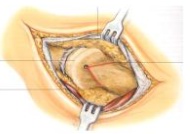

| Osteochondrosis dissecans ; schwere Knorpelschäden |

Offene Knorpel/Knochen-Zylinder-Transplantation |

| Schwere Sprunggelenk-Arthrose | Arthrodese ( arthroskopisch oder offen ) |